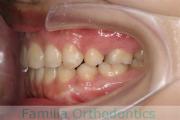

No.23V-478

- 主な症状:

- 叢生

- 年齢:

- 30歳

- 性別:

- 男性

- 抜歯部位

- 上:

- 44済

- 下:

- 8558済

- 主な使用装置:

- FEA 022

- 治療にかかった費用:

- 76万円

右上の歯が重なっているところが邪魔になるとのことで矯正治療を始められた患者さんで、札幌から転院されました。当院で約1年半、15回程度の通院が必要でした。叢生(でこぼこ、凹凸、ガタガタ)が強く、後戻りのリスクが高いケースです。